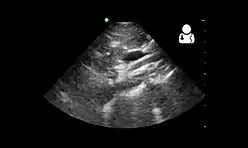

Upper gastrointestinal series showing extreme duodenal dilation (white arrow) abruptly preceding constriction by the SMA.- Ultrasound showing SMA syndrome[19]

Ultrasound showing SMA syndrome[19]

Diagnosis is can be difficult, and usually one of exclusion. SMA syndrome is generally considered only after people have undergone an extensive evaluation of their gastrointestinal tract including upper endoscopy, and evaluation for various malabsorptive, ulcerative and inflammatory instestinal conditions with a higher diagnostic frequency. Diagnosis may follow X-ray examination revealing duodenal dilation followed by abrupt constriction proximal to the overlying SMA, as well as a delay in transit of four to six hours through the gastroduodenal region. Standard diagnostic exams include abdominal and pelvic computed tomography (CT) scan with oral and IV contrast, upper gastrointestinal series (UGI), and, for equivocal cases, hypotonic duodenography. In addition, vascular imaging studies such as ultrasound and contrast angiography may be used to indicate increased bloodflow velocity through the SMA or a narrowed SMA angle.[13][14]